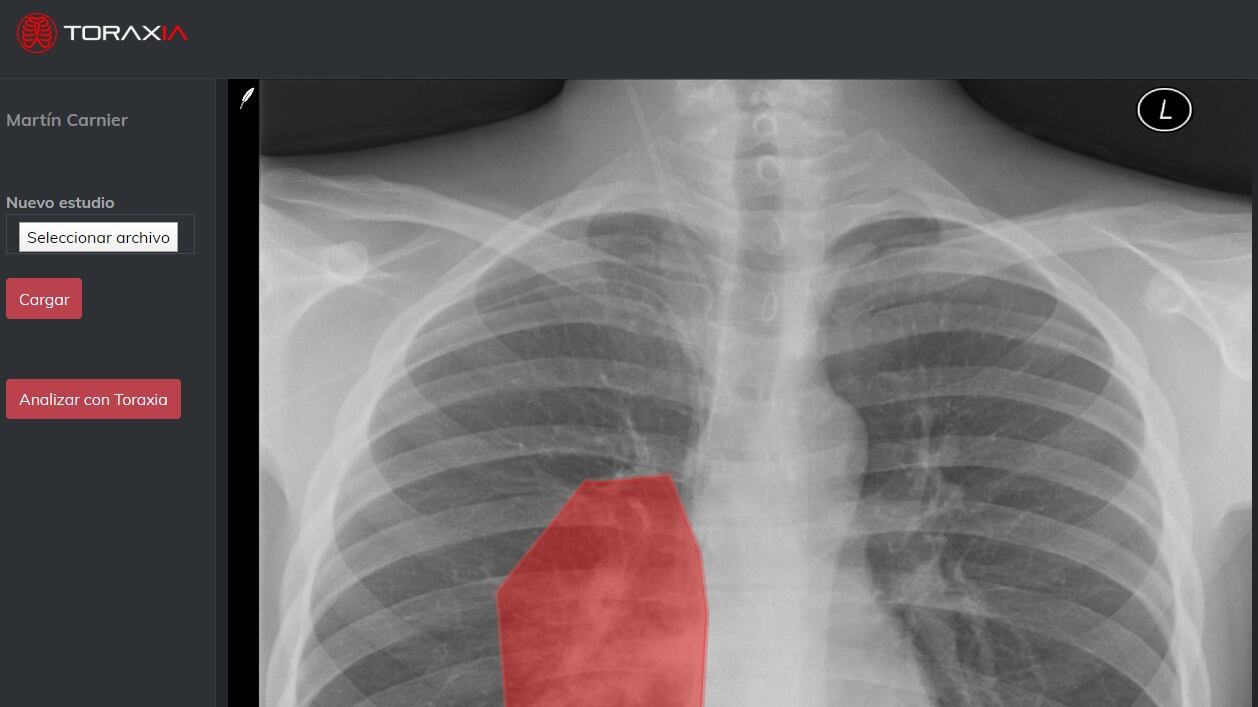

Los médicos pueden acceder a Toraxia desde su computadora o teléfono inteligente, iniciar sesión con su correo electrónico y cargar una imagen DICOM o JPG con la radiografía de tórax. Opcionalmente, pueden indicar los síntomas del paciente para recibir, en segundos, una evaluación con indicadores de riesgo, signos patológicos encontrados y niveles de compromiso pulmonar indicados por mapas de calor.

El equipo de Alumbra-Toraxia, compuesto por médicos y científicos de datos, desarrolló su propio algoritmo de inteligencia artificial basado en más de 200,000 imágenes, de las cuales 30,000 fueron específicamente con patrones sugerentes de COVID-19 disponibles por la Asociación de Radiología de América del Norte. Basada en la nube pública de IBM, la plataforma puede procesar millones de radiografías por semana de hospitales de todo el país, lo que ayuda a reducir el examen de rayos X de horas a minutos, al tiempo que minimiza los posibles errores de diagnóstico y permite a los médicos concentrarse en casos con un nivel más alto de urgencia.